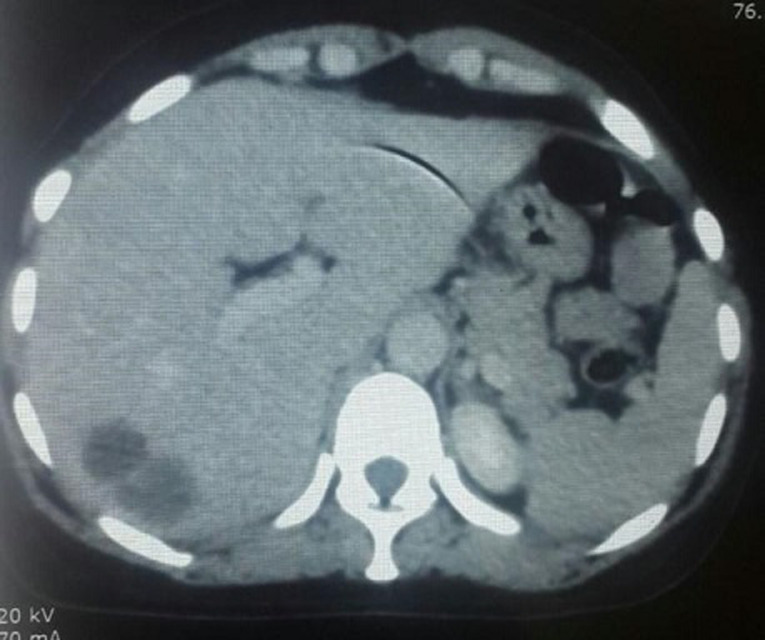

乳腺叶状瘤(PT)是罕见的。它们可以是良性的、边缘性的或恶性的。恶性形式占20-30%的PTs,远处转移在10-26%的病例。化疗是转移性叶状瘤(mpt)的主要治疗手段之一。我们在此报告2015年1月至2017年12月在卡萨布兰卡穆罕默德六世癌症治疗中心治疗的四例乳房mpt病例。患者的平均年龄为25 ~ 45岁。在大多数病例中,发现的方式是由于出现了一个巨大的乳房肿块,所有患者的组织学诊断都是基于乳房切除术标本的检查。3例有肺转移,2例有腋窝淋巴结转移,2例有骨转移,只有1例有肝转移。所有患者均接受化疗。采用阿霉素单药治疗和阿霉素异环磷酰胺(AI)。只有一名患者有非常好的结果,在3个AI方案后放射学完全缓解。乳房mpt预后不良。全身性化疗的作用还有待确定,特别是目前还没有关于最佳化疗方案的数据。

Phyllodes tumors (PT) of the breast are rare. They can be benign, borderline or malignant. Malignant forms account for 20-30% of PTs, with distant metastases in 10-26% of cases. Chemotherapy is one of the main therapeutic weapons for metastatic phyllodes tumors (MPTs). We here report four cases of MPTs of the breast managed at The Mohammed VI Center For Cancers Treatment in Casablanca from January 2015 to December 2017. The average age of patients ranged from 25 to 45 years. The mode of revelation was represented, in the majority of cases, by the occurrence of a huge breast mass and in all patients the histological diagnosis was based on the examination of mastectomy specimen. Three patients had lung metastases, two had axillary lymph-node metastases, two had bone metastases and only one had liver metastases. All patients received chemotherapy. Doxorubicin monotherapy and doxorubicin-ifosfamide (AI) were used. Only one patient had a very favorable outcome, with radiologic complete response after 3 AI regimens. MPTs of the breast have a poor prognosis. The role of systemic chemotherapy is to be defined, especially since there are no data available on optimal chemotherapy regimen.